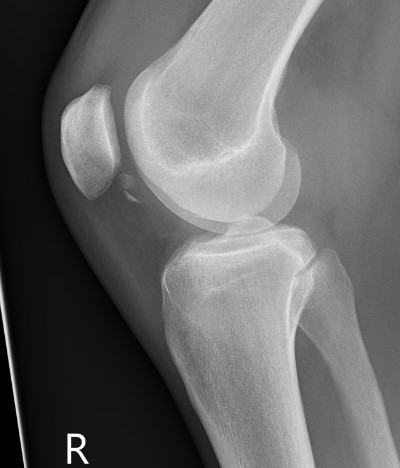

Xray

Look for osteochondral fractures

- lateral xray: notch

Loose body in notch with donor site from patella